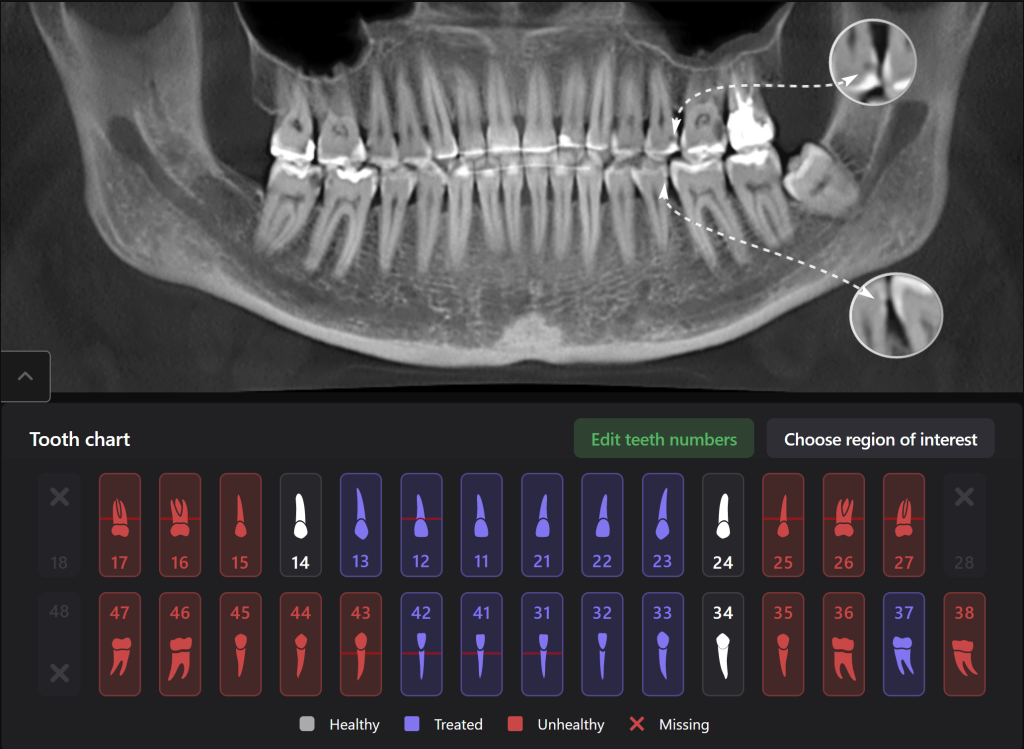

Diagnocat is an artificial intelligence system, one of its advantages being assistance in planning therapeutic dental treatment and identifying signs of caries

Diagnocat determined not only the presence, but also the localization of the focus of radiolucency of enamel and dentin, which was correctly indicated as “signs of caries” in the report

Please note that despite the fact that the radiolucent area is poorly visible when viewing CBCT, Diagnocat reflected in the report the presence of signs of caries and accurately indicated the localization

The presence of a structured report allows the clinician to set up the patient for timely treatment and build a consistent plan for therapeutic dental treatment